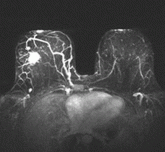

Annual mammography starting at age 40: More talk, less action?

In view of the potential harm, we question annual screening starting at age 40.